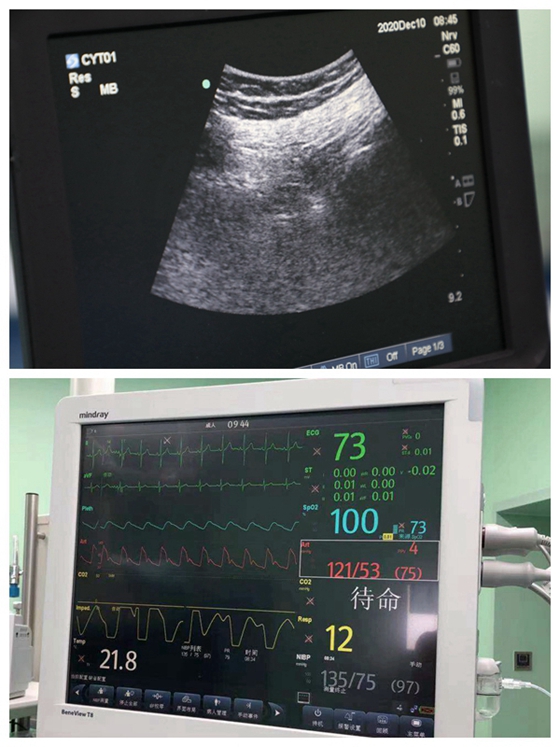

经过紧密讨论,麻醉手术部团队为该患者量身定制了一套最佳的麻醉方案:可视化超声引导下神经阻滞+非插管全麻。随着超声在麻醉操作中应用愈趋成熟,超声在区域麻醉阻滞中发挥着重要作用。麻醉医生要想做好神经阻滞必须对手术区域的神经支配及走向结构清晰。在超声下监测到神经和周围组织,显示穿刺针和局部麻醉药在神经周围的扩散,减少穿刺并发症和神经损伤,增加阻滞成功率。因此可视化超声也被称为是麻醉医生的“第三只眼”。

手术当天,患者入室后,常规心电、有创血压、脉搏氧饱和度监测及BIS监测一并到位。开放输液通路后,孙志华主任和曾覃遥主治医生为患者顺利实施了超声引导下的左侧腰丛+坐骨神经的阻滞。麻醉过程实施过程又快又顺利,患者手术部位完全无痛。手术开始后,为消除患者紧张,把控输注少量镇静药物,患者生命体征平稳,镇痛肌松效果好,外科手术进行得非常顺利。